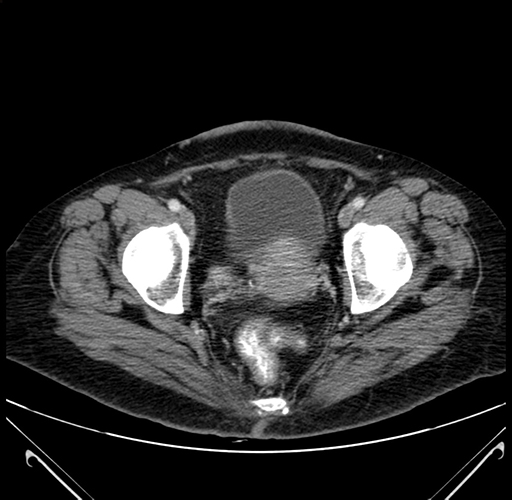

Axial Venous

Coronal Venous

Imaging analysis

Based on your CT findings, which issue(s) would give reason for "planned slowing down moment(s)" in this case?

Considering a standard right hepatectomy procedure, what step(s) of the operation would you do differently in this case?